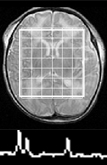

Studies have illustrated prognostic value in determining metabolite ratios between Lactate (Lac), N-acetyl aspartate (NAA), and Choline (CHO) from newborn infants. The goal of this project is to study neonates with signs of HIE by looking at the metabolite ratio differences between Normal and Abnormal outcome groups.  We also perform longitudinal comparisons to determine changes in metabolite ratio across outcome groups.